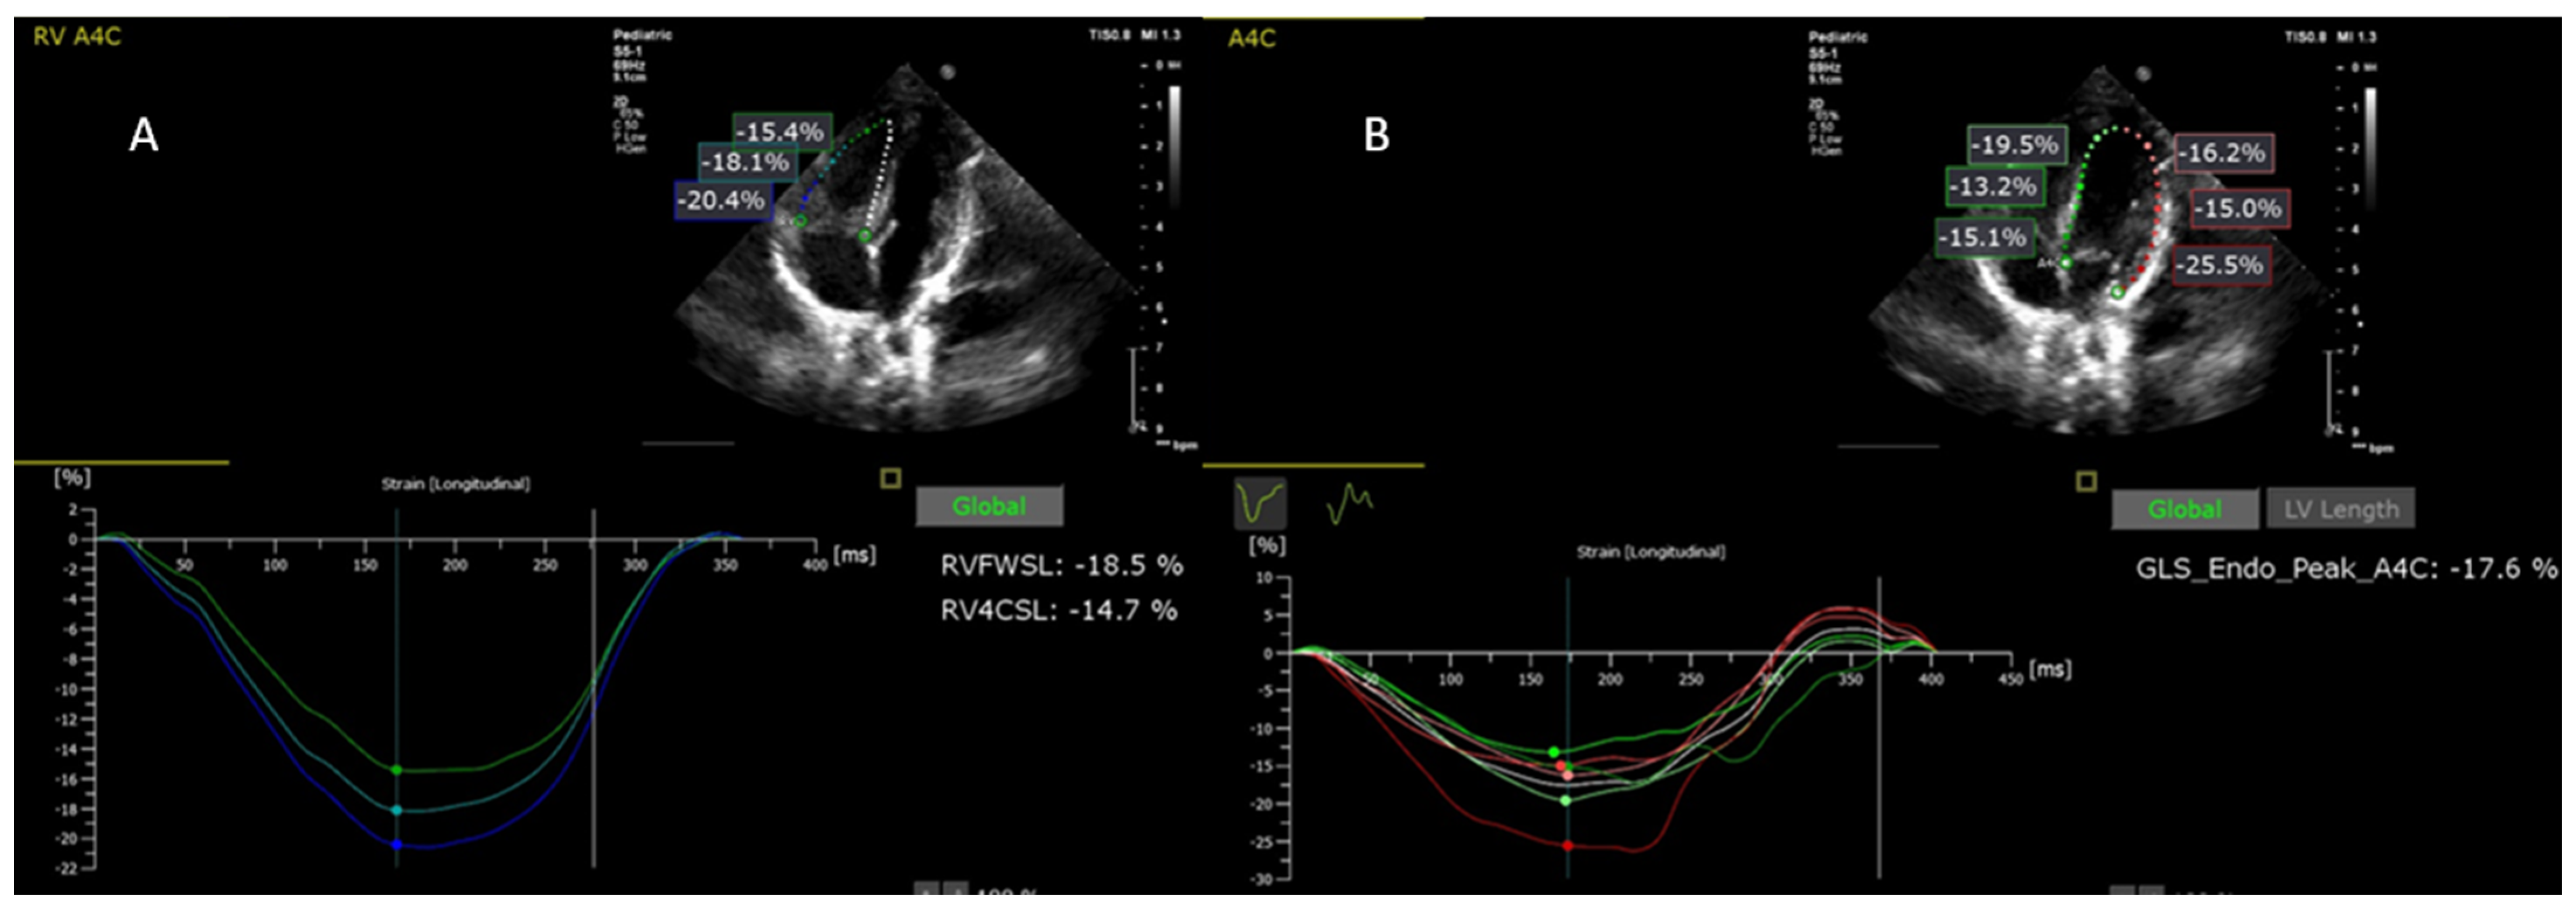

5.2. Comparison of PS Cases with Control Group in Terms of Baseline Regional and Global Longitudinal Strain

5.4. Changes in Baseline and Post-Procedural Biventricular Regional Strains in PS Patients

5.5. Comparison of Longitudinal Strain and Conventional Ecocardiographic Parameters Measured before and after Interventionin in PS Patients